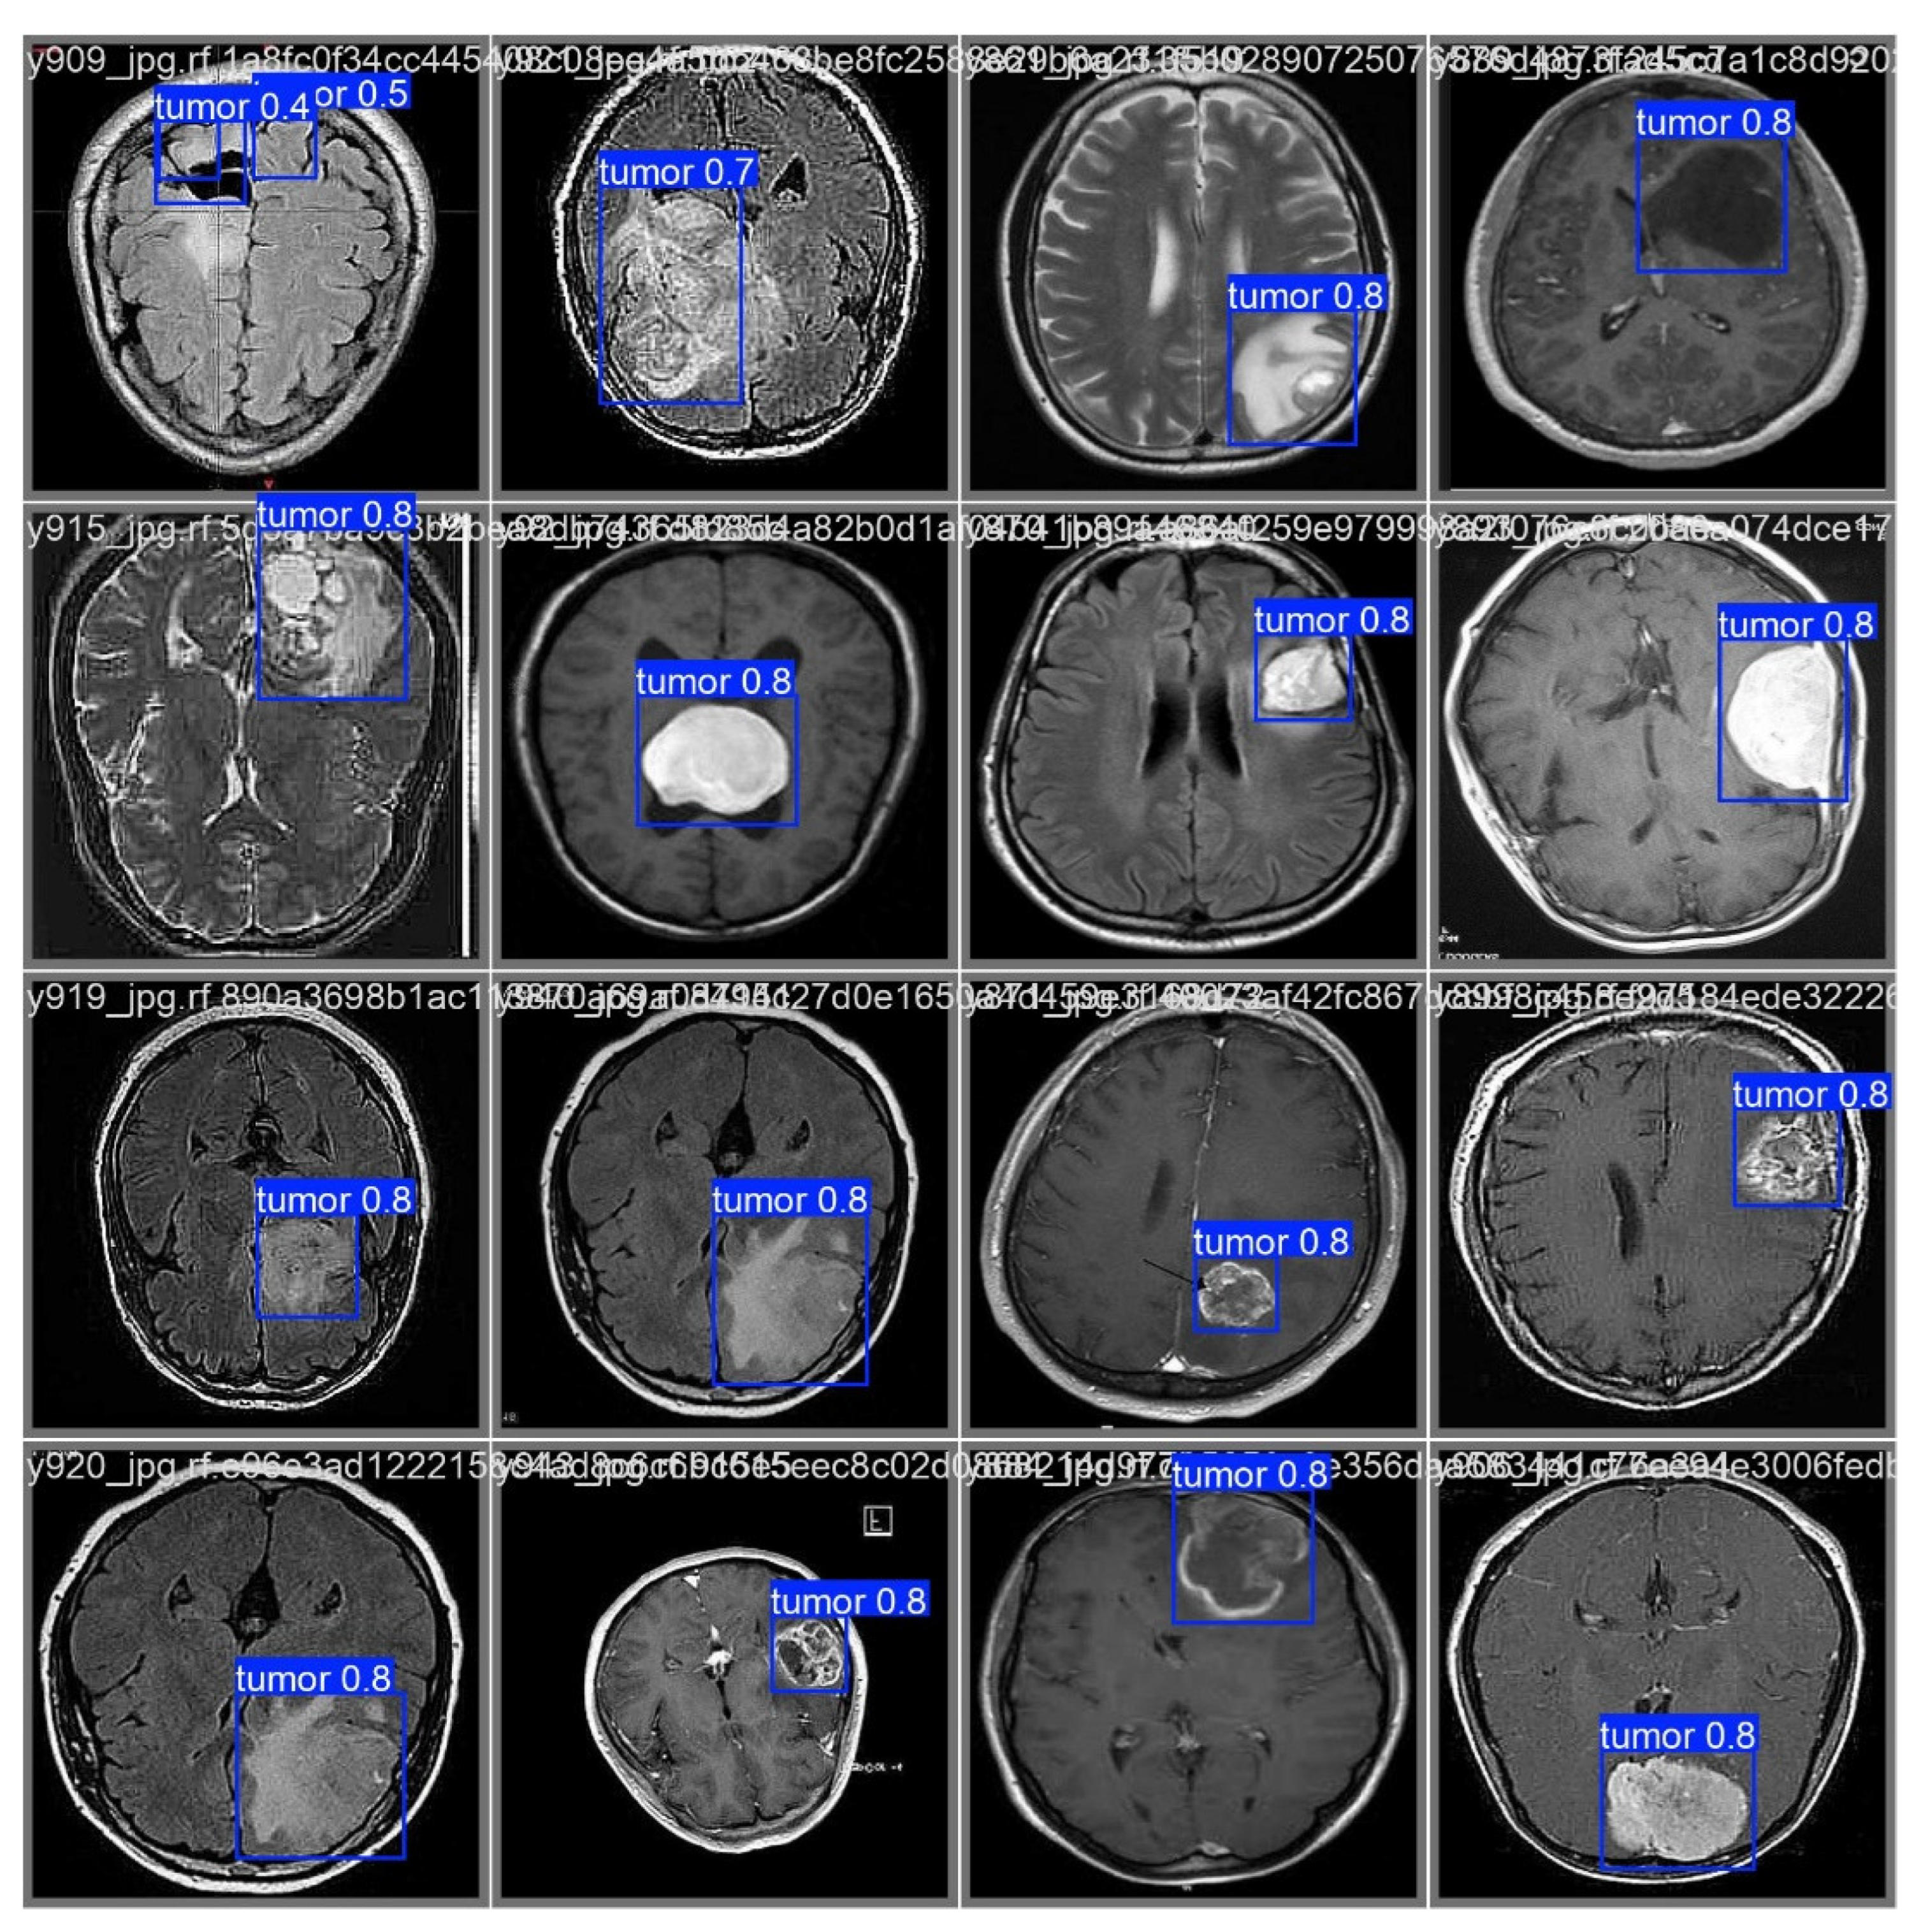

As illustrated in Figure 6, after processing through the proposed model, it automatically identifies regions associated with cancer by incorporating blue bounding boxes. Additionally, each detection is accompanied by a confidence percentage, indicating the certainty level of the model’s predictions.

To evaluate the model’s ability to generalize brain tumor detection beyond a specific cancer type, tumors of various sizes were considered. The results indicate that the model correctly identifies affected areas regardless of variations in size or tumor coloration. In some cases, tumor regions appear white, in others gray, and some even combine both shades. This behavior suggests that the model possesses a high generalization capacity, accurately detecting cancerous regions regardless of their size, color, or location within the image. This effectively demonstrates the “Theoretical Foundations and Applications of Deep Learning Techniques” through computer vision.

Figure 6. Predictions examples.